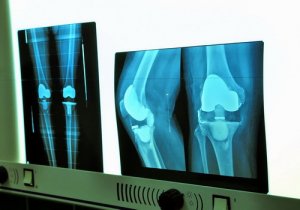

Эндопротезирование коленного сустава в Израиле

Коленный сустав часто повреждается при артрите, в частности при остеоартрите, травмах колена, аутоиммунных заболеваниях, разрушающих хрящевую ткань. Главная задача эндопротезирования коленного сустава – избавление пациента от боли и восстановление опорно-двигательной функции.

Операция по замене коленного сустава в Израиле предполагает имплантацию протеза из сверхпрочных износостойких материалов. Он может сгибаться под углом 155°, что позволяет пациенту свободно двигаться, забыв о том, что у него эндопротез. Система индивидуального подбора имплантата позволяет создать модель, в точности совпадающую с «родным» суставом. Замена коленного сустава в Израиле проводится под контролем навигационной системы новейшего поколения, которая дает возможность хирургам в режиме реального времени отслеживать эффективность вмешательства.

В клинике Ассута проводятся операции полного или частичного эндопротезирования коленного сустава. Установка имплантатов может быть осуществлена путем проведения эндоскопической, малоинвазивной операции, что позволяет избежать обширного хирургического вмешательства и уменьшить кровопотери.